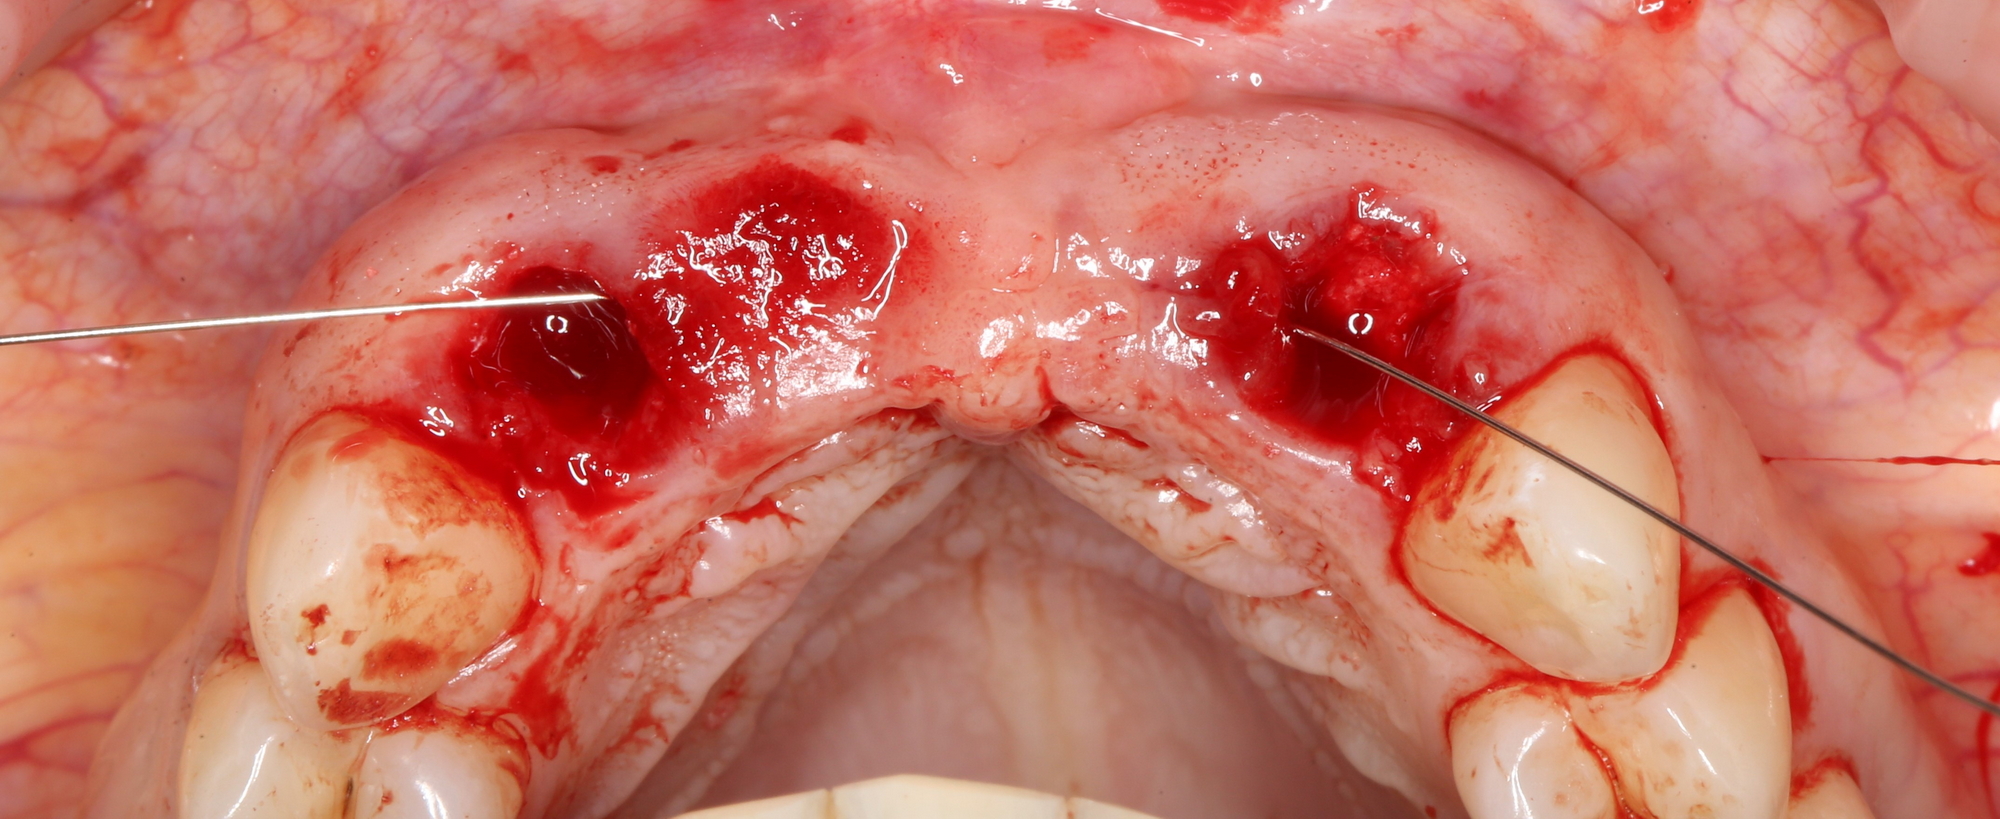

Следующий шаг — подготовка ложа под соединительнотканный аутотрансплантат или, проще говоря — под пересадку десны. Мы решили минимизировать травму, поэтому будем создавать подслизистый тоннель:

Это довольно просто, хотя и требуется известная аккуратность. Мы используем обычные инструменты для синуслифтинга:

Вы уже догадались, что мы не планируем дополнительных разрезов — весь объём работы мы проведём через лунки зубов. Таким образом, мы снизим травматичность нашей операции и, как следствие, риск возможных осложнений.

Создание тоннеля в области центральных резцов занимает 10-15 минут. В последующем, мы проведём и зафиксируем в нём соединительнотканный аутотрансплантат, который создаст необходимый для эстетики объём мягких тканей: